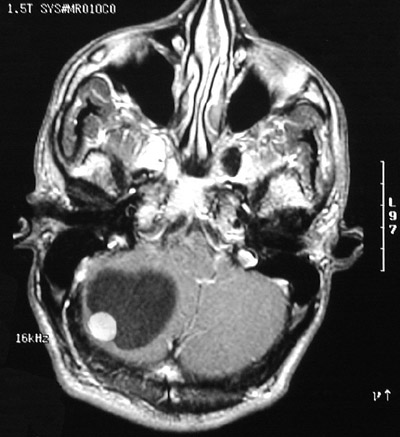

| This enhanced MRI scan in axial view demonstrates a cystic mass with a brightly enhancing mural nodule. This is a cerebellar hemangioblastoma. Posterior fossa masses in adults are uncommon, but this is one possibility. Many hemangioblastomas are cystic. |